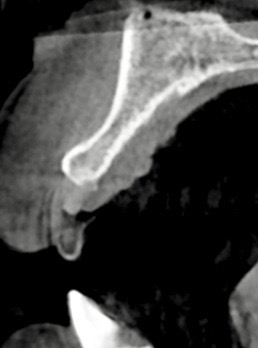

下記の症例は骨幅が狭小でこのままではインプラント治療を行う事ができず、また適切な補綴物を装着できない為、見た目が悪くお手入れしにくい被せ物を装着する事になります。

その為、当医院では様々な骨造成手技を用い、長期的に安定したインプラント周囲骨そして、審美的な結果を左右する結合組織移植を同時に行い、周囲環境を改善していきます。